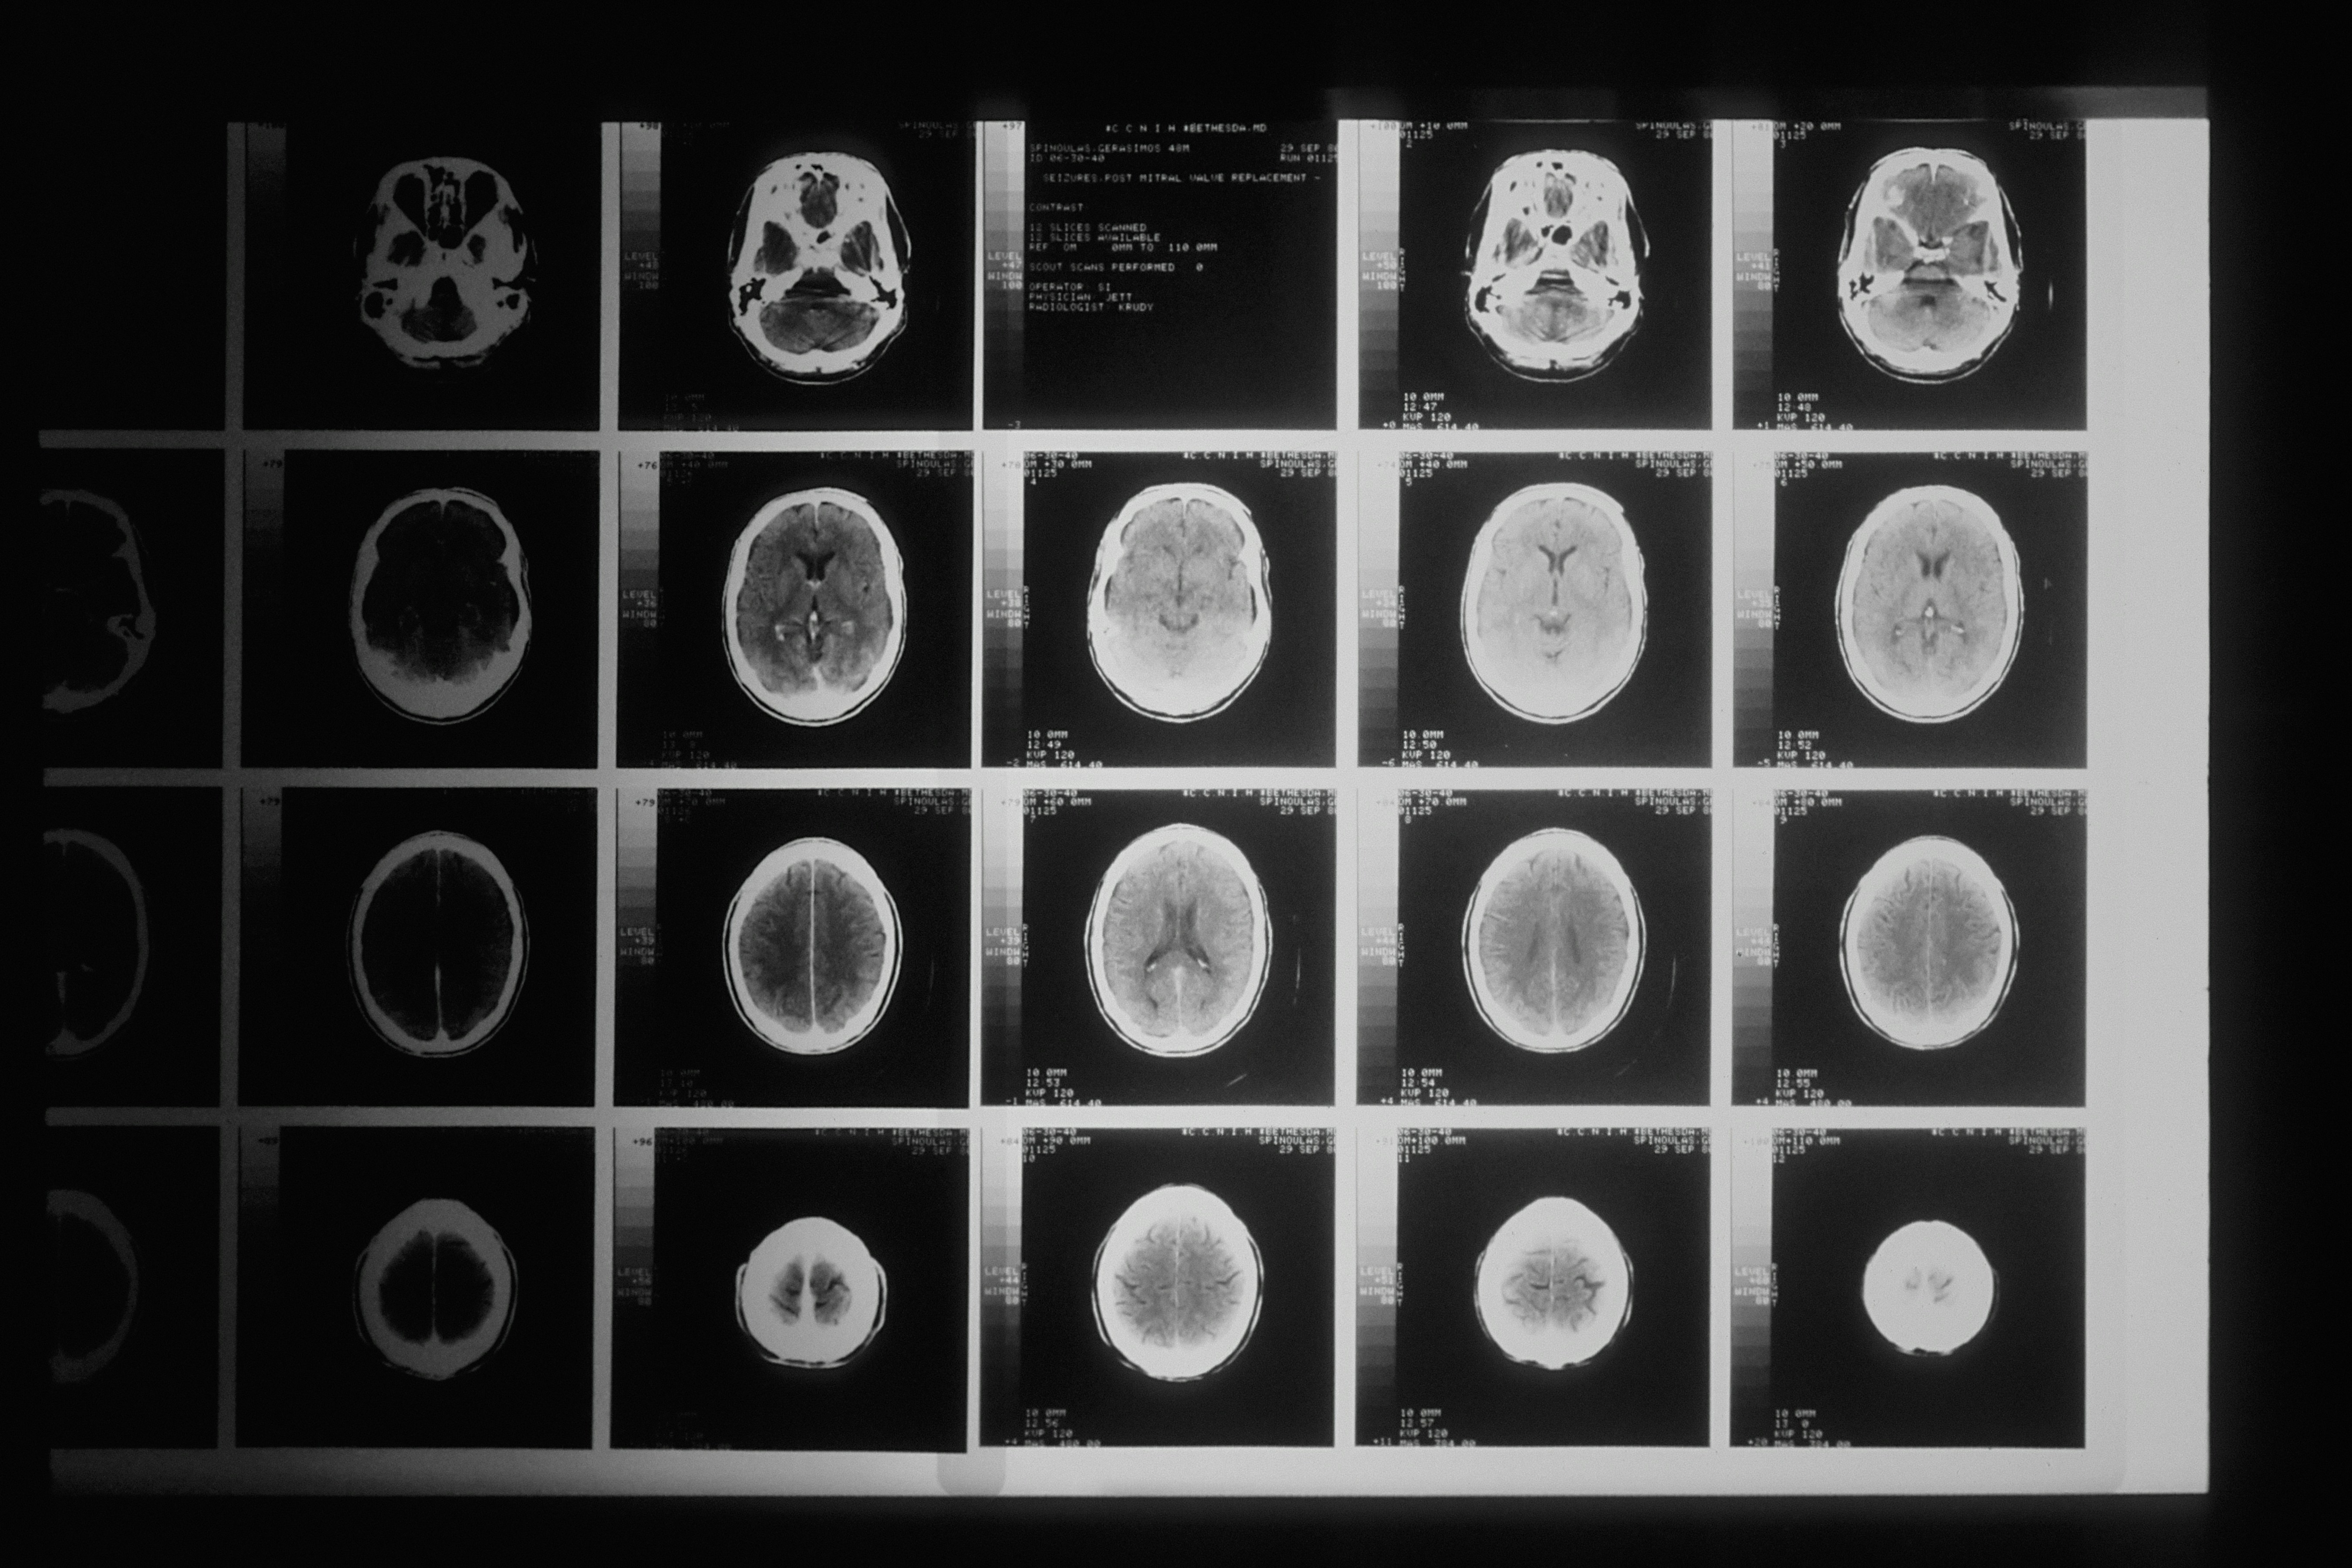

Rezultati snimanja pokazali su da ima tumor na mozgu "veličine avokada" – kaže da su joj liječnici rekli da vjerojatno raste 15 godina.

"Testirali su mi sluh, ali nisam mogla ništa čuti. Rezultati moje magnetske rezonance pokazali su da imam tumor veličine avokada koji pritišće moj mozak. Bio je to strašan trenutak – samo sam željela da se vratim kući svojoj obitelji."

Nakon operacije, biopsija je potvrdila da je njezin tumor veliki akustični neurinom – rijedak benigni tumor koji pogađa otprilike dvoje od 100.000 ljudi, prema podacima Britanskog udruženja za akustične neurinome.